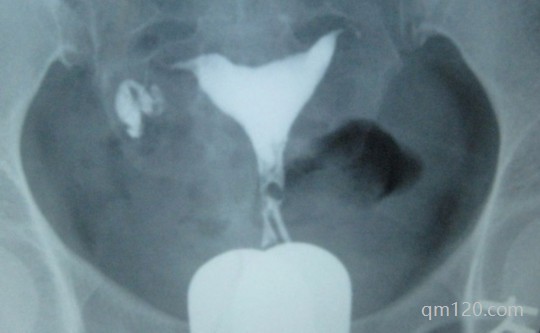

輸卵管造影是一種用于檢查女性輸卵管是否通暢的放射性檢查。在這個(gè)過(guò)程中醫(yī)生會(huì)通過(guò)宮頸注入一種含碘的造影劑到子宮和輸卵管中,然后使用X射線進(jìn)行成像。對(duì)于一些女性來(lái)說(shuō)...